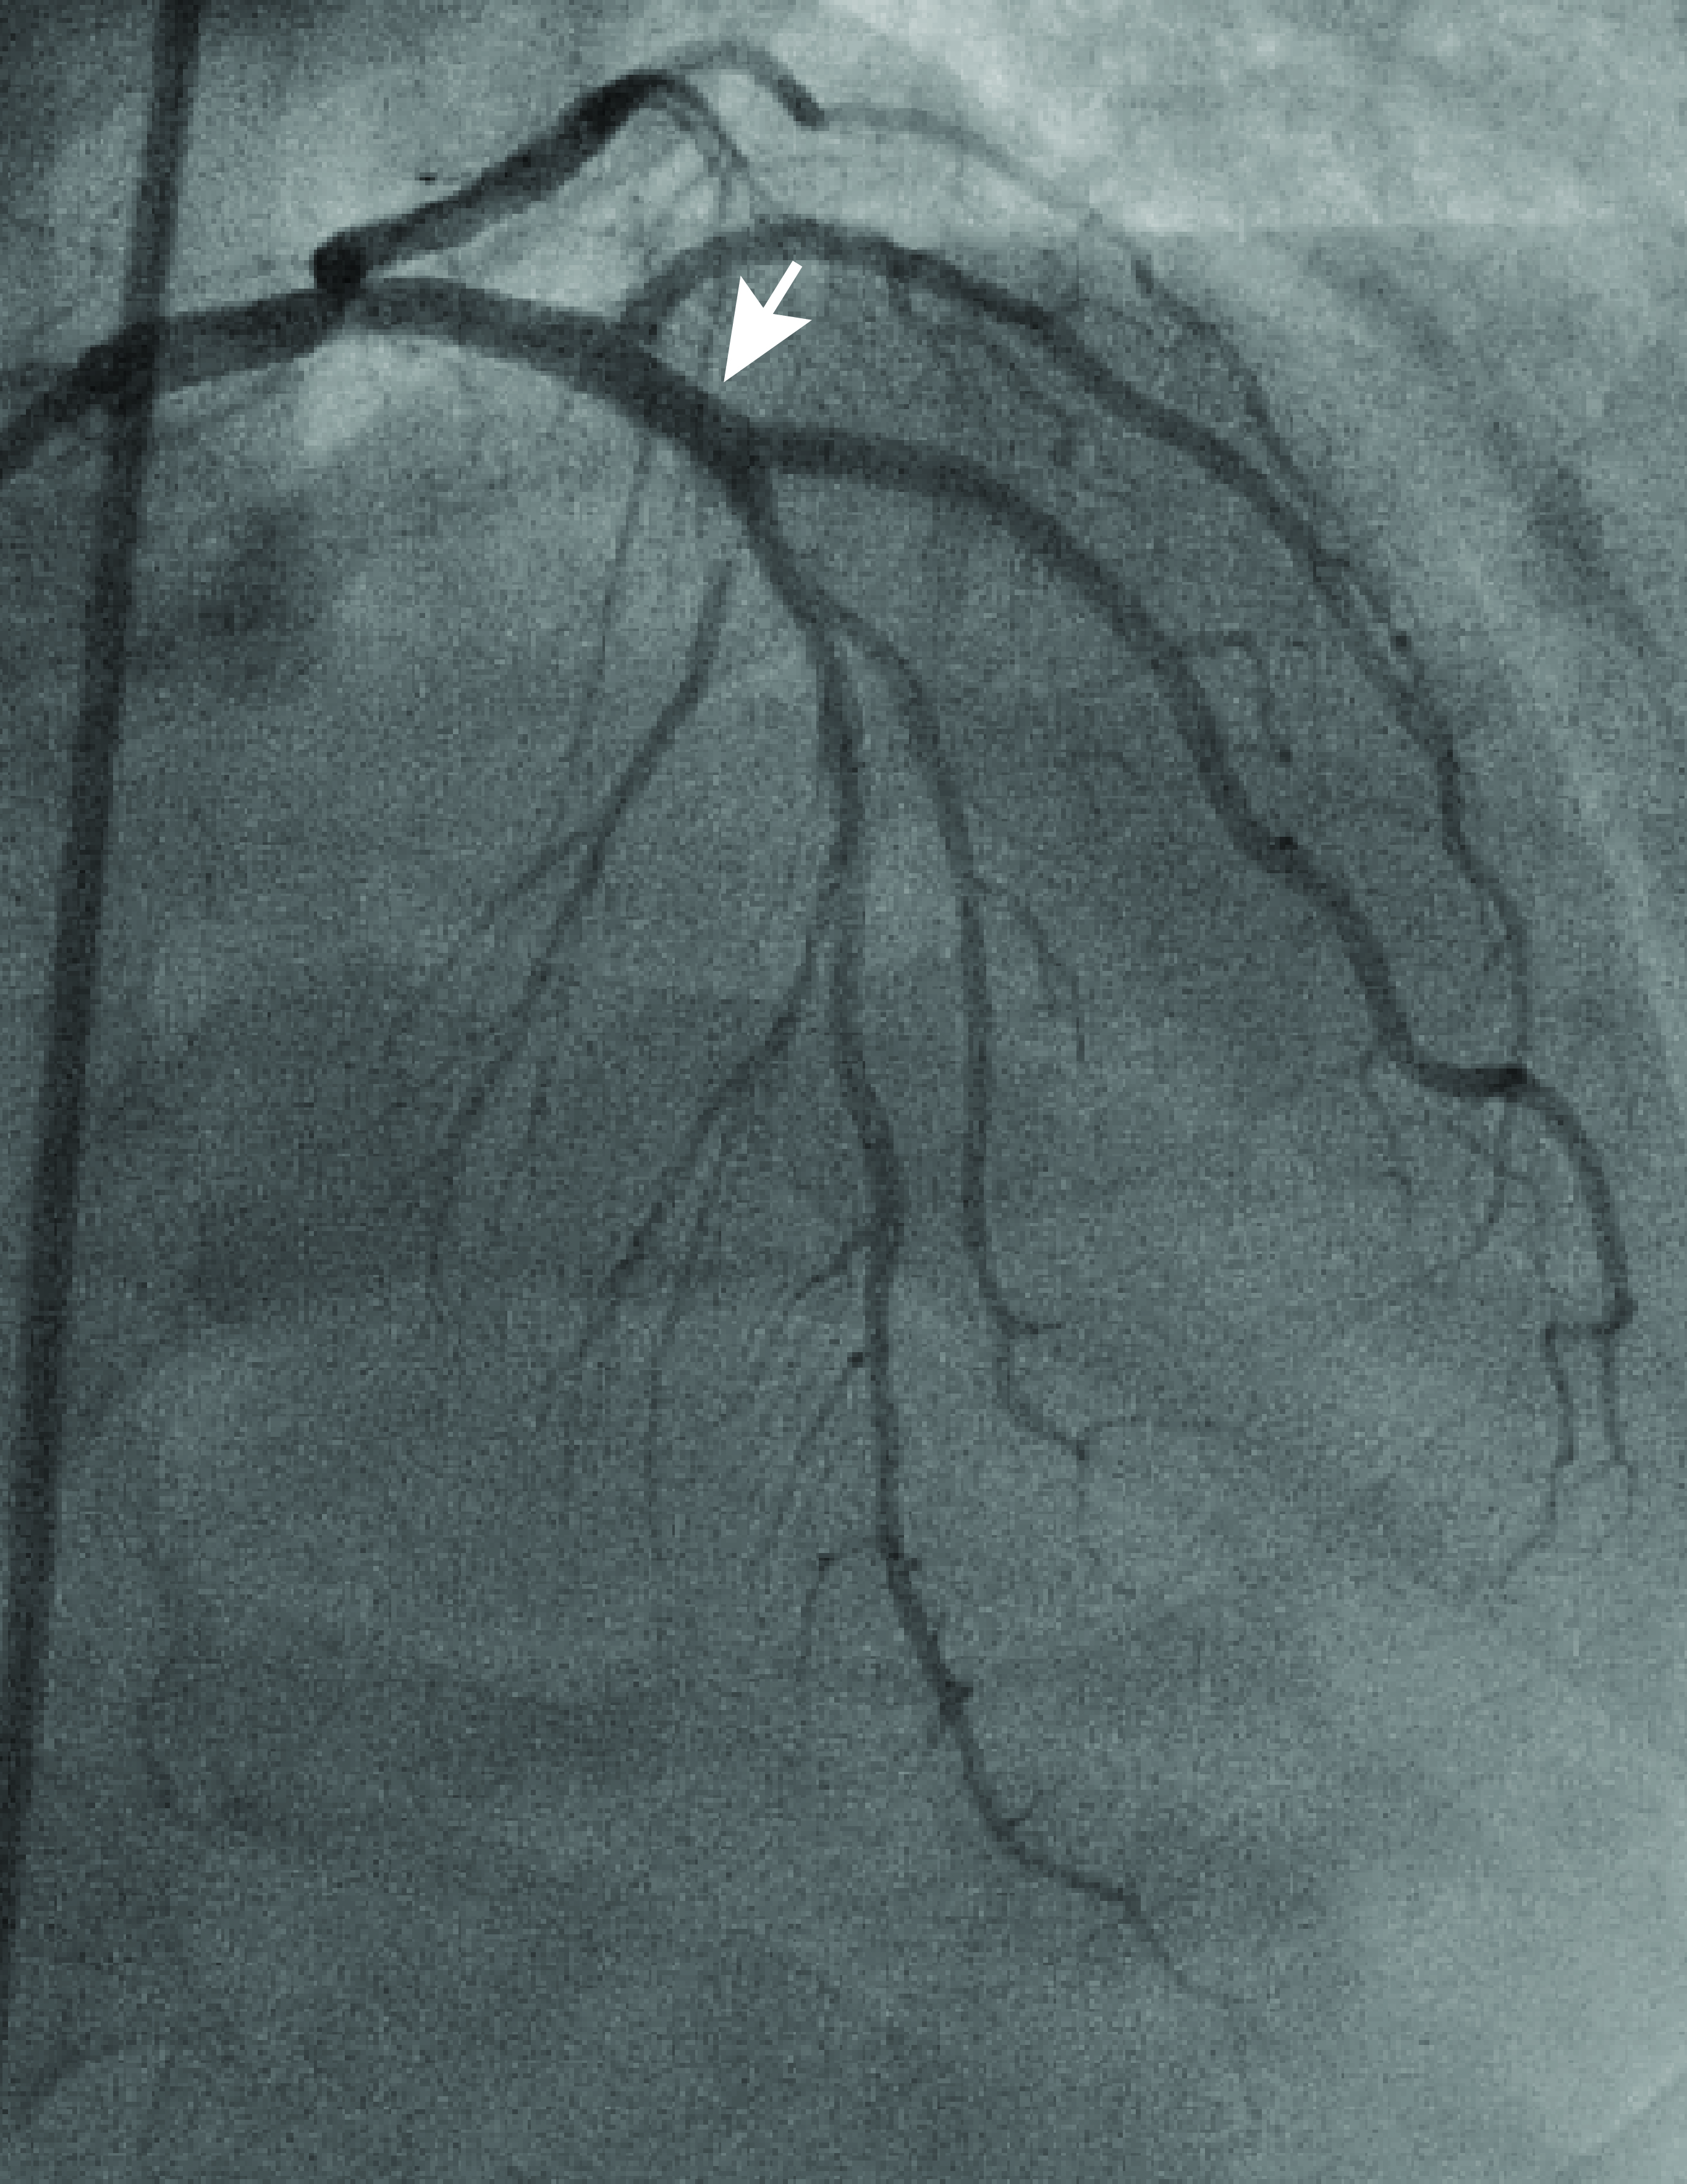

A novel framework for fluid/structure interaction in rapid subject-specific simulations of blood flow in coronary artery bifurcations

Abstract PDF FIG 1 Odgovor recenzentu A Rezime rada ID 2792 A NOVEL FRAMEWORK FOR FLUID/STRUCTURE INTERACTION IN RAPID SUBJECT-SPECIFIC SIMULATIONS OF BLOOD FLOW IN CORONARY ARTERY BIFURCATIONS Fig 2 Fig 3 Fig 4 Fig 5 Fig 6 Fig 7 Fig 8 Fig 9 Fig 10 -